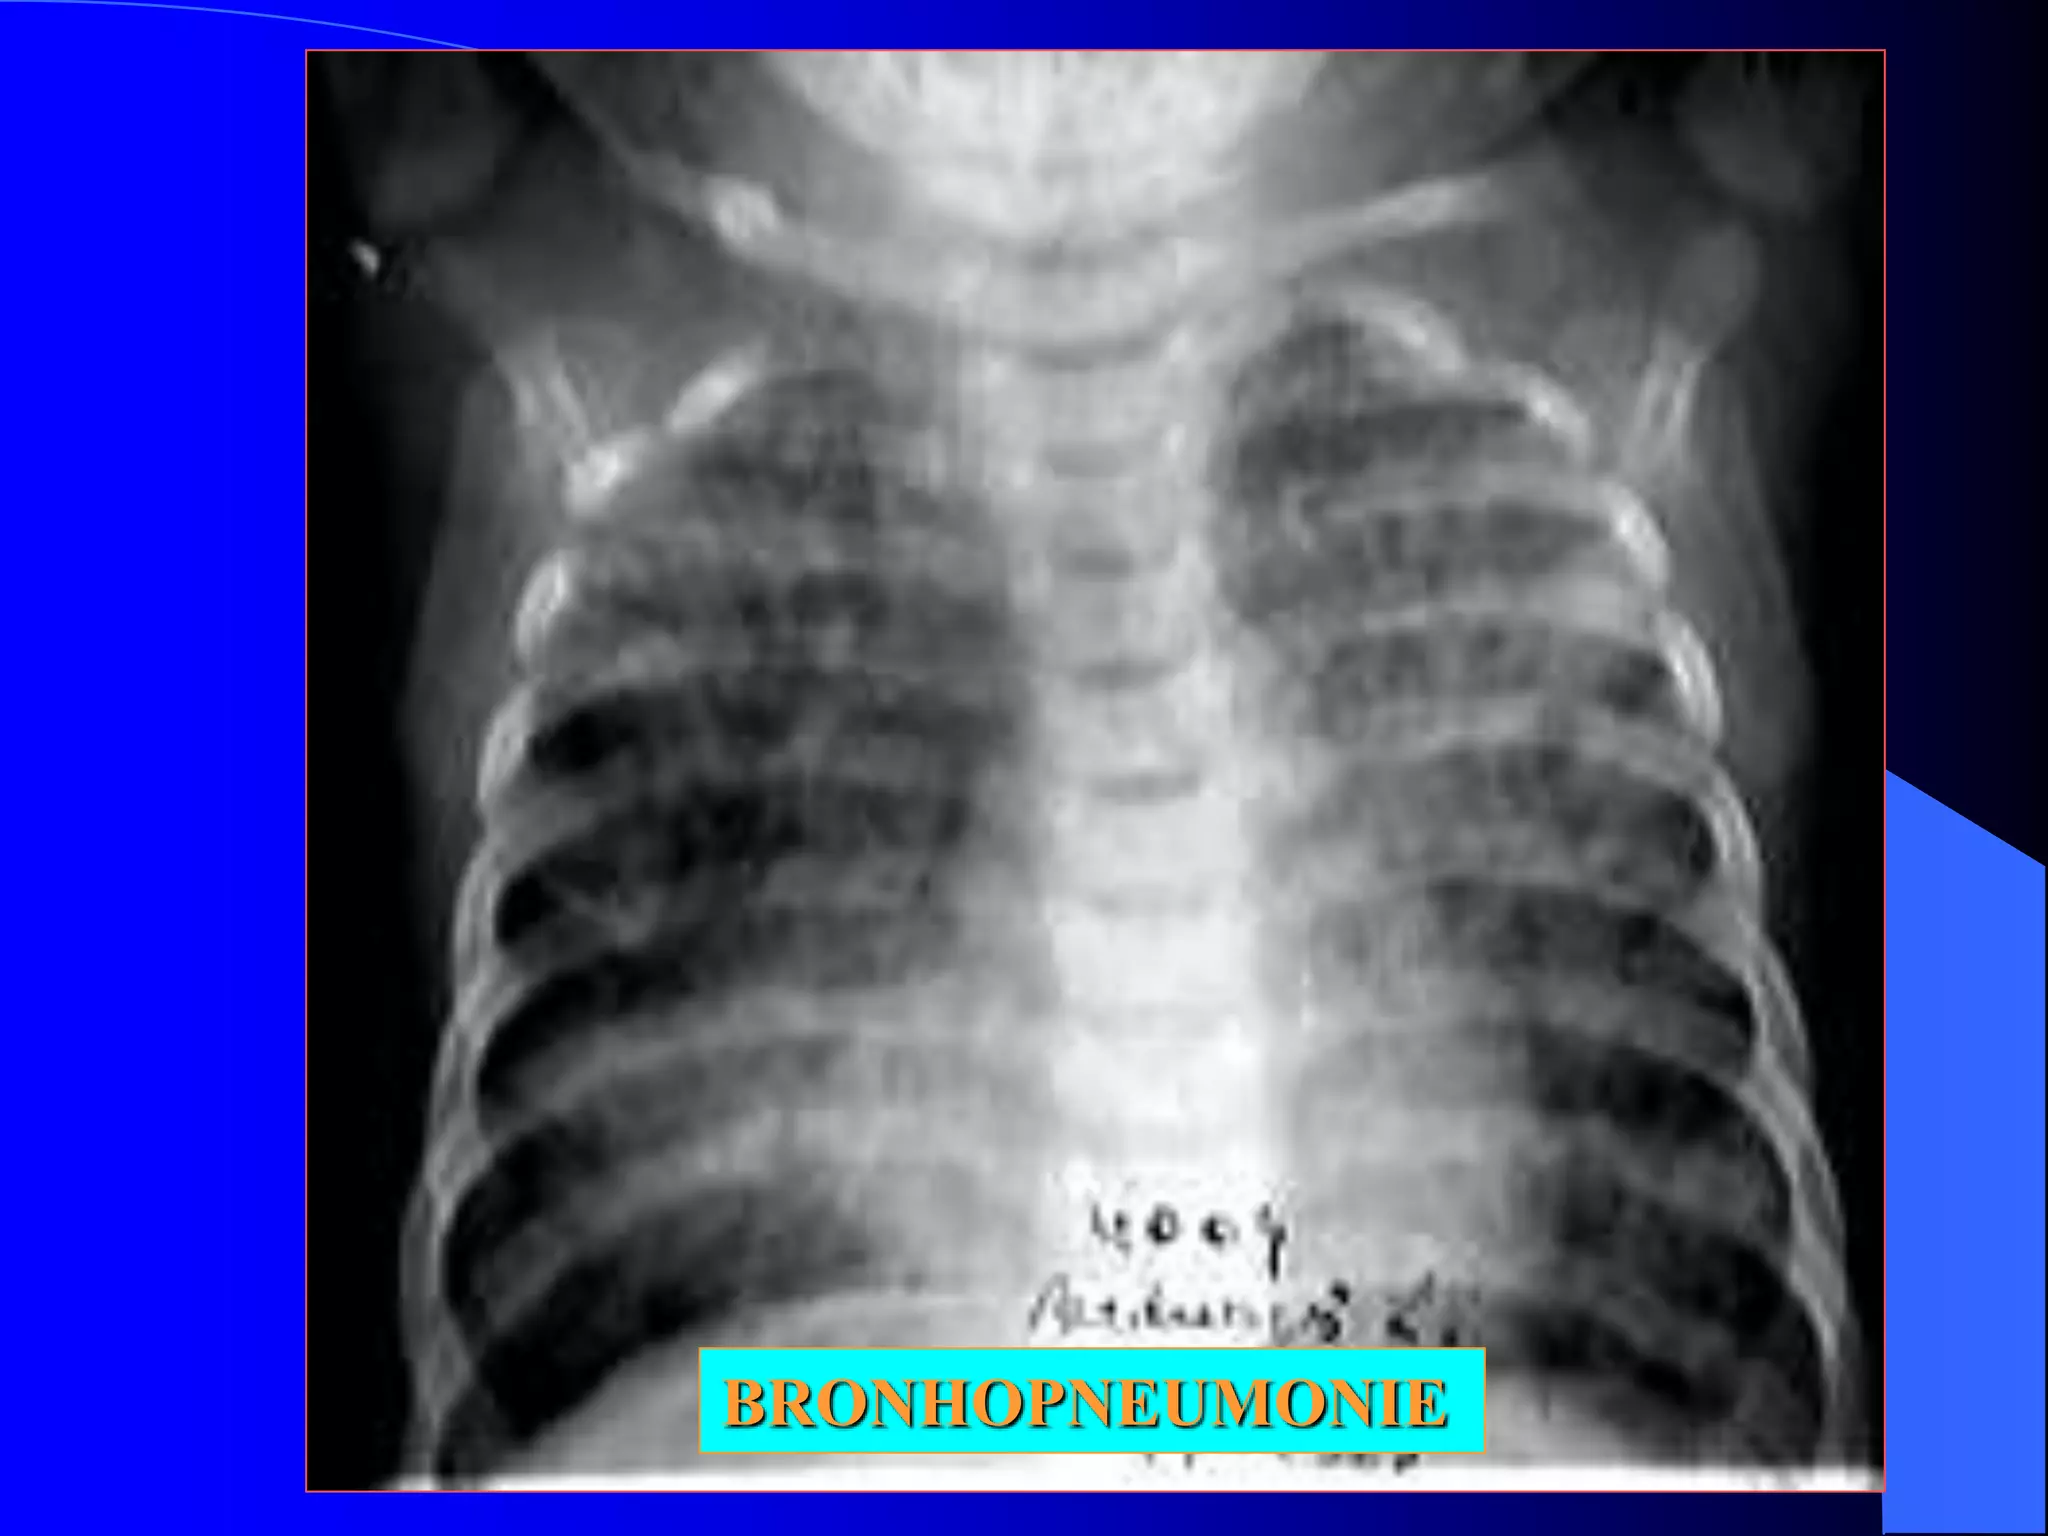

Radiologic: opacitati rotunde/ovalare, contur estompat, diseminate

opacităţi multiple de intensitate medie,

contur flou, tendinţă la confluare,

mai numeroase în câmpurile pulmonare

medii şi bazale

opacităţi difuze, cu tendinţă la confluare

pe ambele arii pulmonare mai frecvent

in câmpurile pulmonare superioare ca şi

ân regiunile parahilare

BRONHOPNEUMONIE